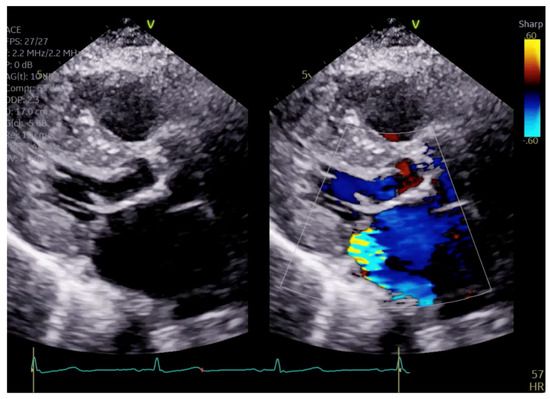

Figure 7.

TEE demonstrating posteriorly directed MR.

Given the concern for primary MR, a transesophageal echocardiogram (TEE) was performed for further assessment. The study showed prolapse, chordal rupture and partial flail of the A3 leaflet with an area of non-coaptation and severe MR (Figure 6, Supplementary Video S4). Quantification using the proximal isovelocity surface area method revealed an effective orifice area of 0.46 cm2 and a regurgitant volume of 80 milliliters with notable systolic pulmonary vein flow reversal, consistent with severe Carpentier class II MR from prolapse and flail (Figure 7, Supplementary Video S5) [2]. This highlights the role of TEE and 3D imaging in assessing for SAM-independent causes of primary MR in patients with HCM. A TTE alone can miss these anatomical findings, especially in medial (A3 or P3) or lateral (A1 or P1) mitral scallops.